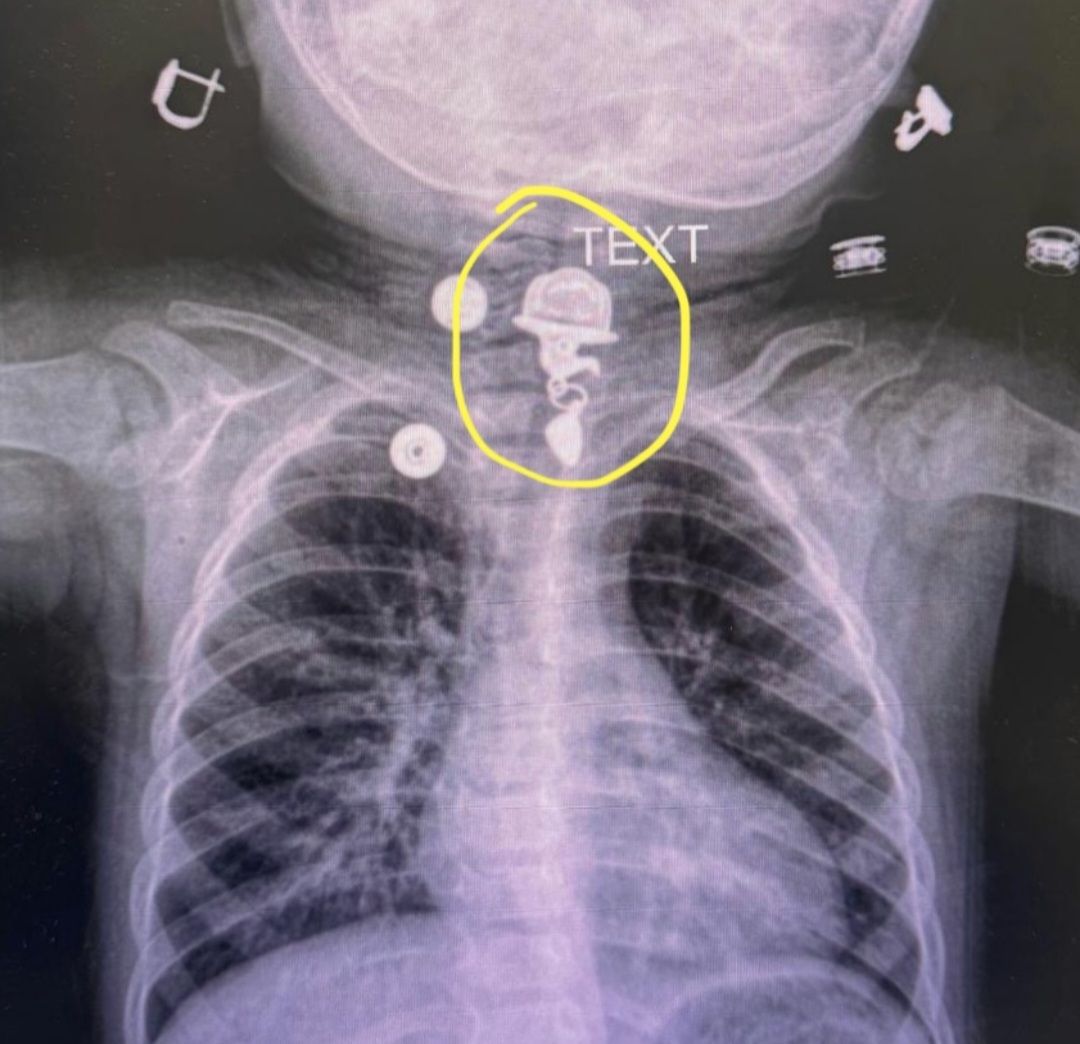

Türkiyədə 16 aylıq uşağın boğazında yad cism qalıb.

"Bu şəkildə mənə müraciət edən 16 aylıq uşaq xəstənin döş qəfəsinin rentgen görüntüsü göstərilir. İşarələdiyim sahədə qida borusunun yuxarı hissəsində metal boyunbağı ucu görünür. Təəssüf ki, uşaq ailəsinin xəbəri olmadan onu udub. Belə hallarda qida borusunda olan yad cisimlər mədə-bağırsaq tıxanmasına və ya perforasiyasına səbəb ola bilər. Eynilə, yad cisimlər traxeyaya daxil olduqda, qəfil tənəffüs çətinliyinə və tənəffüs dayanmasına səbəb ola bilər ki, bu da həyati təhlükə yaradan vəziyyətlərdir.

Ailələr yad cisimlərin daxil olmasına və məişət qəzalarına daha diqqətli olmalıdırlar. Evdə yad cisimləri çıxarmağa çalışmamalı və görünsə belə, barmaq və ya digər aləti ağıza soxaraq onları çıxarmağa çalışmamalıdırlar. Çünki yad cismin daha da içəri itələmə riski var. Belə hallarda ailələr üçün ən yaxşı yanaşma birbaşa təcili yardım şöbəsinə getmək və yazəng etməkdir. Təcili vəziyyətdə həkimə müraciət edin".